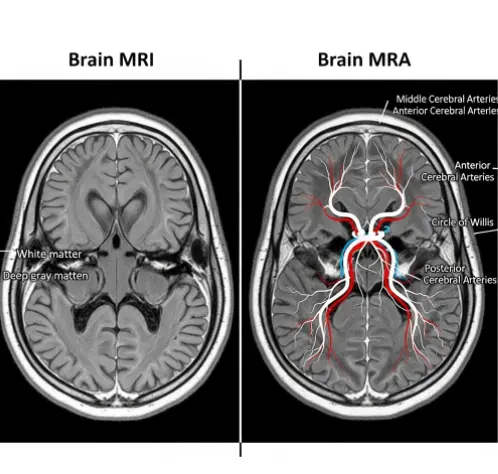

- 뇌 MRI (자기공명영상): 집의 '내부 인테리어'를 보는 검사입니다.

- 방 구조는 잘 되어 있는지, 벽에 곰팡이는 없는지, 가구가 부서지진 않았는지를 봅니다. 즉, 뇌의 '실질적인 살(조직)' 모양을 찍습니다.

- 뇌 MRA (자기공명혈관조영술): 집 벽 속에 숨겨진 '수도 배관(보일러 배관)'만 따로 보는 검사입니다.

- 물이 흐르는 파이프가 꽉 막히진 않았는지, 혹은 파이프가 낡아서 꽈리처럼 부풀어 오르진 않았는지를 봅니다. 즉, 뇌의 '혈관'만 집중해서 찍습니다.

MRI(Magnetic Resonance Imaging)는 강력한 자석의 힘을 이용해 뇌의 단면을 사진처럼 찍어내는 검사입니다.

MRA(Magnetic Resonance Angiography)에서 'A'는 Angiography, 즉 혈관 조영술을 뜻합니다. 뇌 조직은 투명하게 처리하고 오직 '혈관의 길'만 입체적으로 보여줍니다.